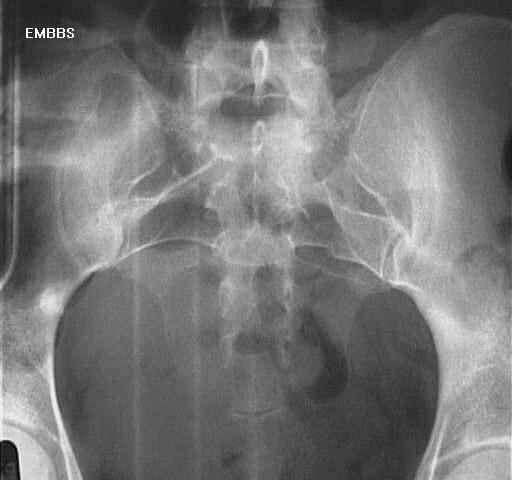

• Radiographs

• only show 30% of sacral fractures

• recommended views

• AP

• lateral

• effective screening tool for sacral fractures

• often of poor quality

• findings

• L4 or L5 transverse process fractures

• asymmetric foramina

• anterior pelvic ring disruptions

• stepladder sign

• seen on AP view

• results from displacement with overriding of transverse fracture fragments

• indicates disruption of anterior sacral foramina and lumbrosacral facets